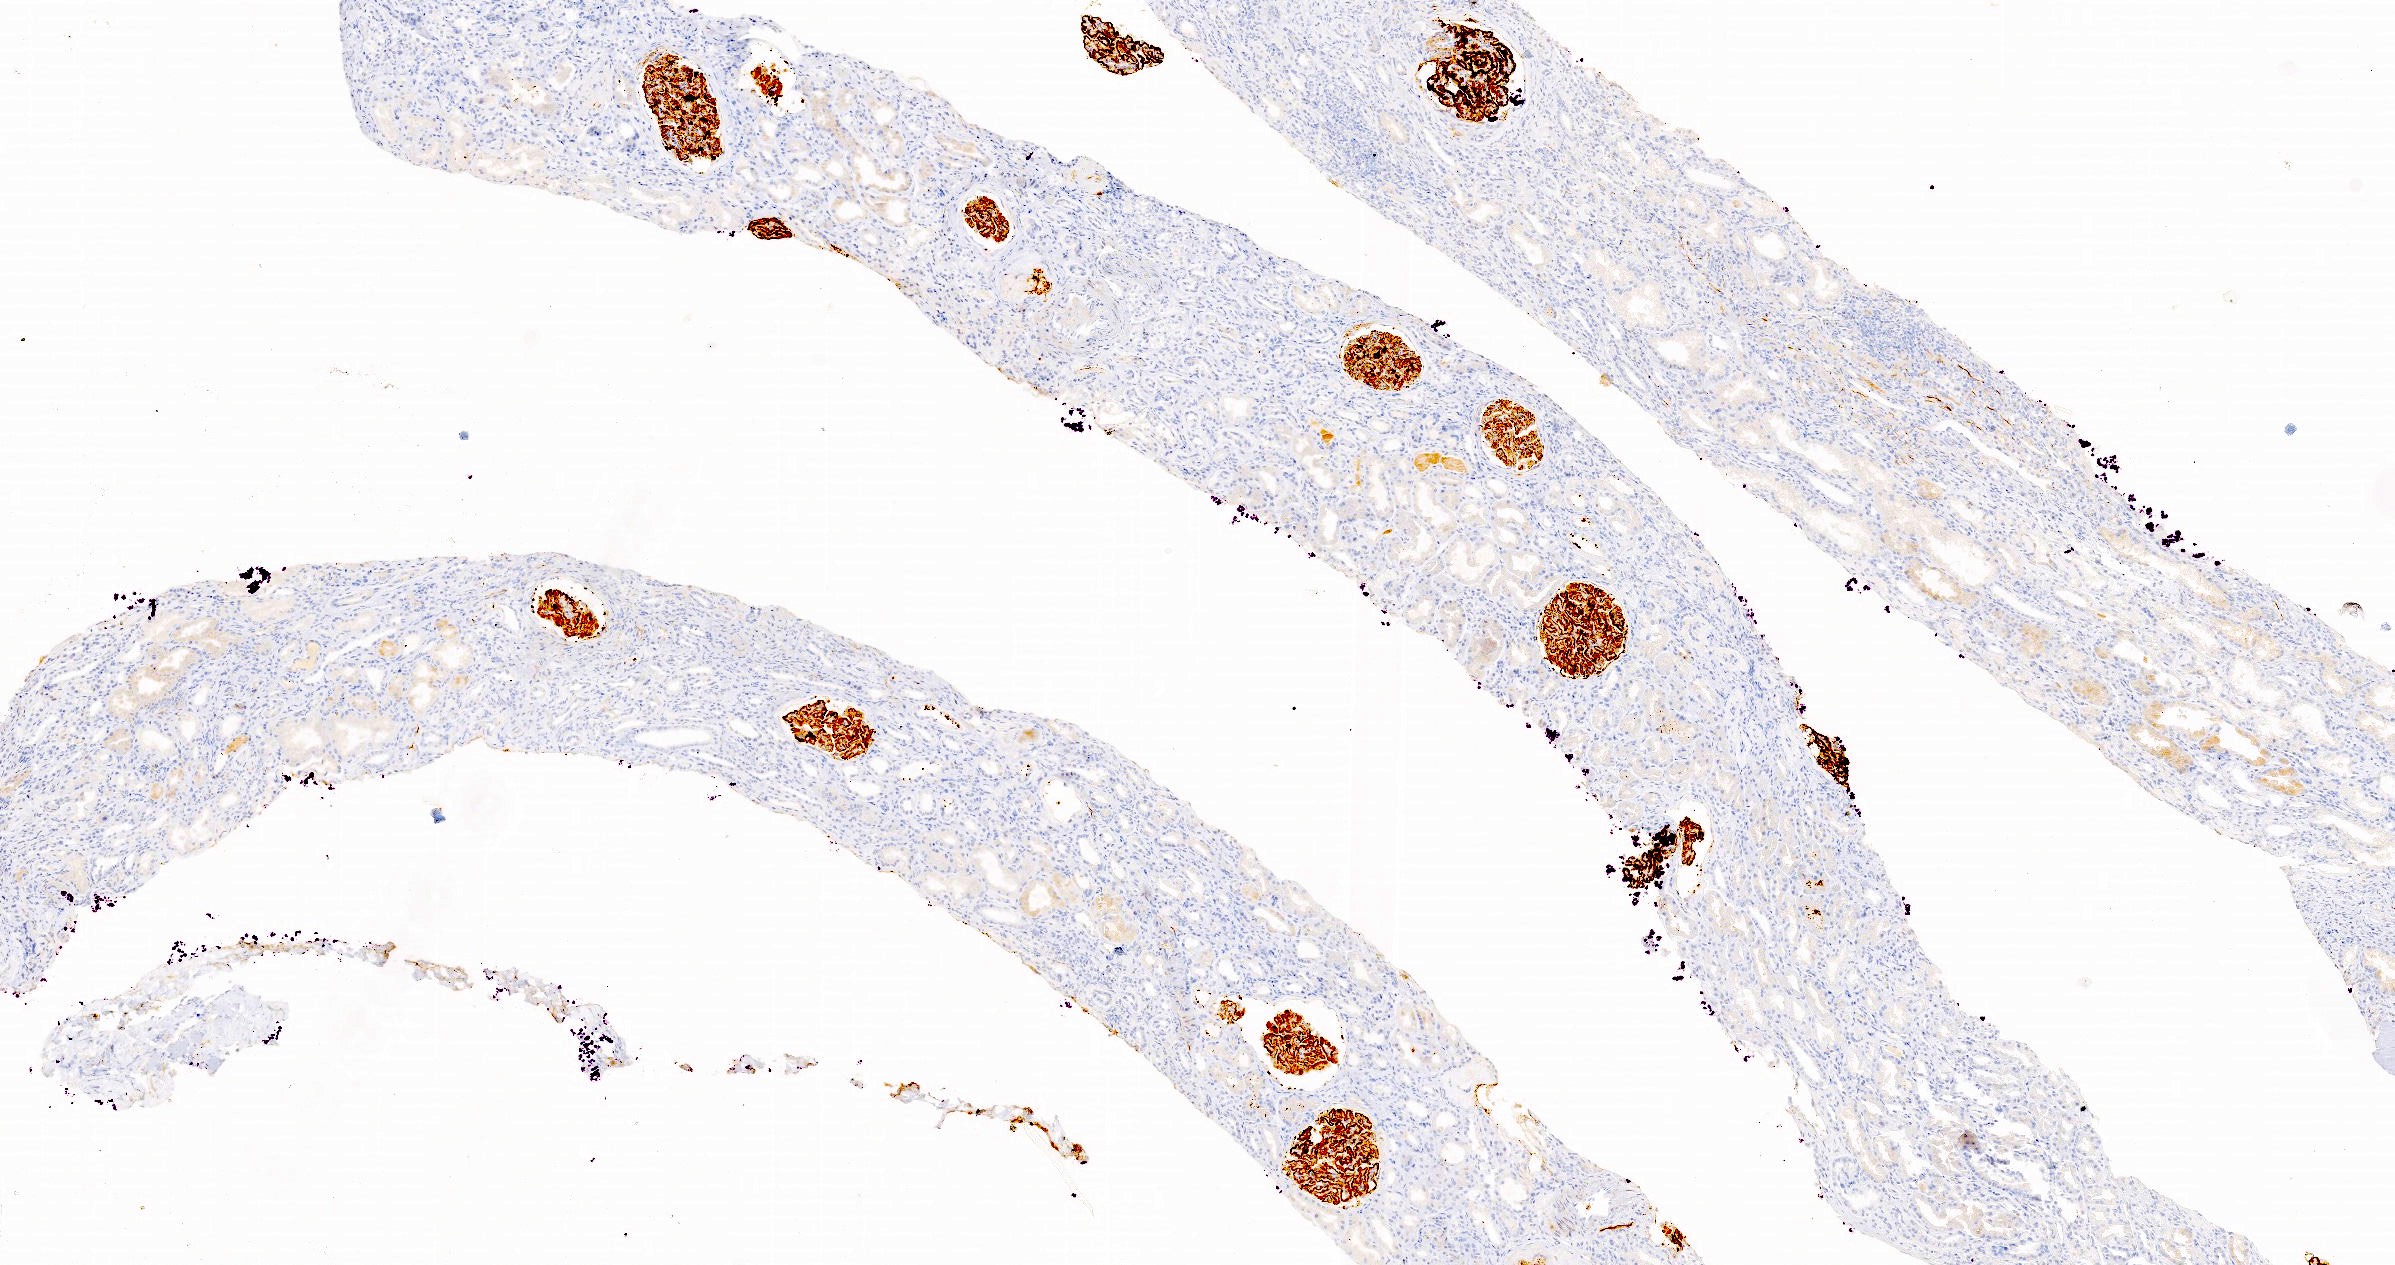

Microscopic (histologic) images

Microscopic (histologic) description

- Glomeruli may appear entirely normal in early disease (stage 1)

- Thickening of glomerular basement membrane

- Subepithelial spike formation or vacuolated appearance on PAS or Jones silver stain (Colvin: Diagnostic Pathology - Kidney Diseases, 2nd Edition, 2015, Zhou: Silva's Diagnostic Renal Pathology, 2nd Edition, 2017)

Positive stains

- PLA2R and IgG4: intense global and granular staining of glomerular basement membrane (Appl Immunohistochem Mol Morphol 2021;29:414)